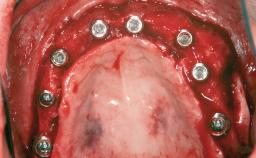

| # of Teeth | 5 |

| # of Implants | 3 |

| Bone Augmentation | Horizontal|Staged|Vertical |

| Augmentation Materials | Autogenous chips|Autogenous block(s)|Xenogenous |